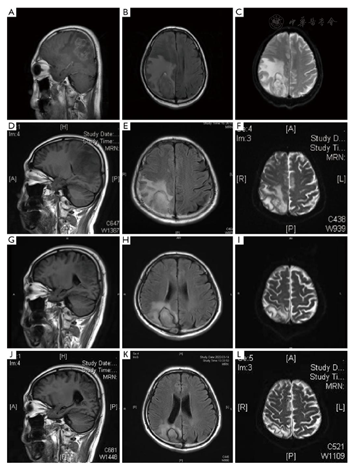

入院后检查血常规示:白细胞计数5.92×109/L(3.97×109~9.15×109/L)正常:中性粒细胞计数4.76×109/L(正常:2.00×109/L~7.00×109/L),(1,3)-beta-d-葡聚糖试验、半乳甘露聚糖试验均正常,降钙素原<0.02 ng/ml。患者淋巴细胞亚群显示T细胞以及自然杀伤细胞下降,CD4/CD8:0.2(正常:1.0~2.5),CD4计数:90/μl(正常:384~1346/μl),CD4/CD45RA:0.6%(正常:15.0%~25.0%),同时患者合并低丙种球蛋白血症,免疫球蛋白G(immunoglobulin G,IgG):7.62 g/L(正常:8.6~17.4 g/L)。头颅磁共振影像(平扫):右侧枕顶叶占位伴大片水肿,建议颅脑MR增强检查,左侧额叶、两侧半卵圆区缺血灶。2021年8月3日头颅磁共振影像增强:右侧枕顶叶占位伴大片水肿,考虑恶性,结合病史,转移性肿瘤可能(图1)。给予"甘露醇、甘油果糖、速尿脱水降颅压处理"。患者症状进一步加重,出现步态不稳加重,左侧肢体无力且感觉迟钝。2021年8月6日腰椎穿刺:测颅压大于300 cmH2O(80~180 cmH2O,1 cmH2O=0.098 kPa),脑脊液常规:透明度清,潘氏试验(+),红细胞1×106/L,白细胞<1×106/L;脑脊液生化:脑脊液糖4.0 mmol/L(2.2~3.9 mmol/L),脑脊液氯(干式法)108 mmol/L(118~132 mmol/L),脑脊液蛋白(干式法)1733 mg/L(<500 mg/L)。真菌荧光染色检查:阴,真菌染色荧光涂片:直接涂片未发现细菌,抗酸染色涂片:未找到抗酸杆菌。脑脊液PMseq病原微生物高通量基因检测报告(该病原体基因组上的位置分布)提示:根毛霉属(Rhizomucor,检出序列数3842)、微小根毛霉(Rhizomucor pusillus,检出序列数3771)。样本测序数据及病原理论灵敏度:检出总序列数43 797 028;真菌(100 MB)理论灵灵敏度(copies/ml):1.00E+00(图2)。期间患者症状持续加重,出现嗜睡、左侧肢体肌力减退,肌力1级。

应用治疗第2天患者意识恢复清醒,体温正常,且左侧肌力也逐日好转。用药1周左右肌力恢复至4级。2周左右肌力完全恢复正常水平。8月31日复查头颅MR病灶均较前好转(图1)。后患者症状恢复,精神状态好,肌力完全恢复正常。考虑进一步治疗患者中枢毛霉感染,于2021年10月14日在静脉全身麻醉下行颅内脓肿引流术及活检。病理结论:(右顶)染色结果,符合毛霉菌感染。免疫组化:CD2(部分+)、CD20(-)、CD68(组织+)、GFAP(组织+)、Olig2(-),特殊染色PAS(+),银染(+)。2021年11月15日复查头颅MRI增强提示病灶较前缩小(图1)。目前选择应用泊沙康唑口服降阶梯治疗。2022年3月复查头部MRI显示感染病灶改善(图1)。